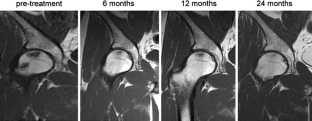

The overall clinical outcomes were improved in 83%, unchanged in 7% and worsened in 10% for group A; and improved in 77%, unchanged in 13% and worsened in 10% for group B. THA was performed in 10% of group A and 10% of group B (P = 1.000). Significant improvements in pain and function of the hip were noted in both groups (P < 0.001), however, the differences between the two groups were not significant (P = 0.400, 0.313). On MR images, the lesions showed progression in 10%, regression in 47% and unchanged in 43% in group A, and progression in 7%, regression in 53% and unchanged in 40% in group B (P = 0.830).

Fig. 1

Fig. 2